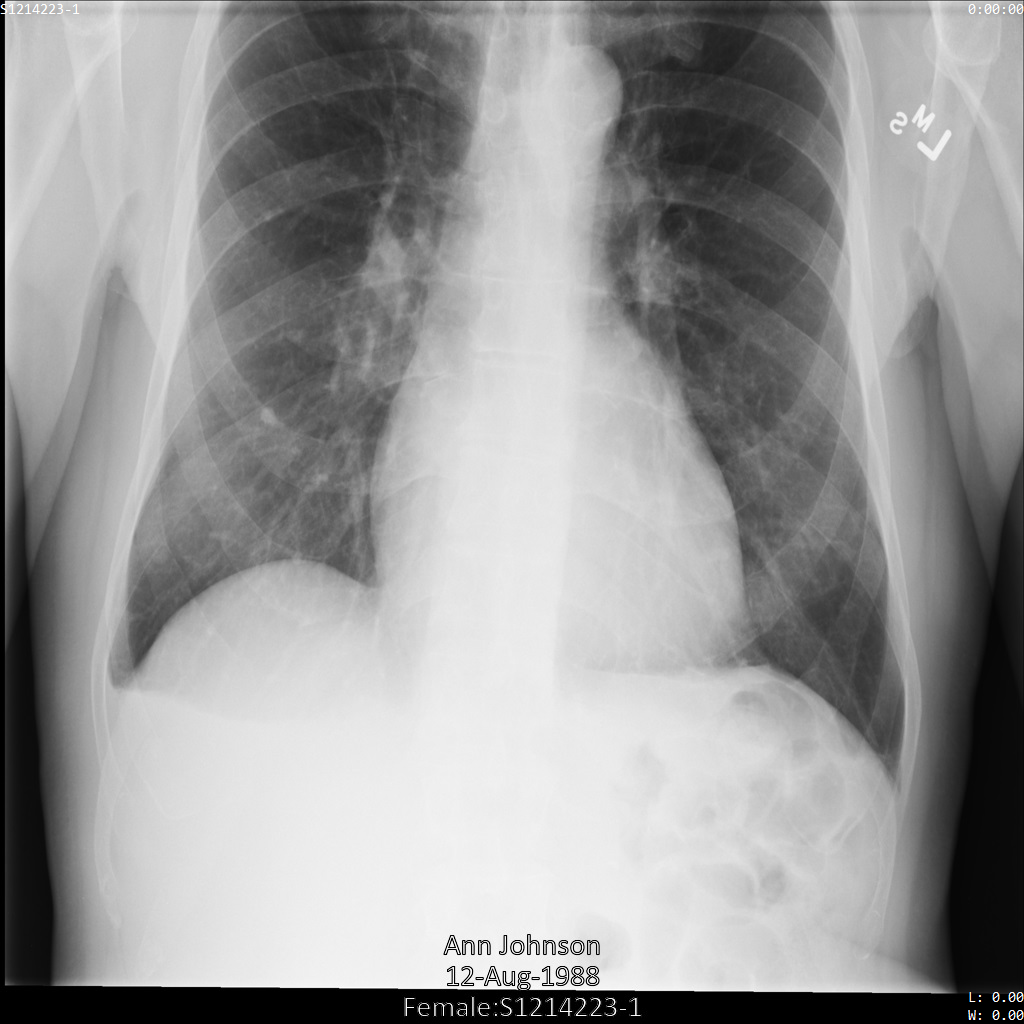

Dopo aver inviato l'immagine all'API Cloud Healthcare, l'immagine viene visualizzata

come segue. Dei tag forniti nell'elenco di rimozione, solo PatientBirthDate

viene rimosso nell'immagine, in quanto è l'unico tag dell'elenco di rimozione che

corrisponde ai metadati visibili nell'immagine.

Mentre il PatientBirthDate nell'angolo in alto dell'immagine è stato oscurato in base alla configurazione nell'elenco di rimozione, le PHI personali incorporate nella parte inferiore dell'immagine rimangono. Per rimuovere anche

il testo integrato, consulta Oscuramento del testo integrato nelle immagini.